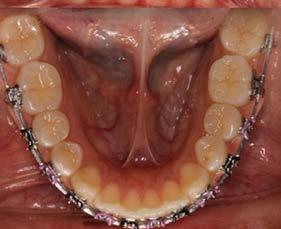

Caso clínico: paciente femenino de 19 años, patrón dolicofacial, perfil convexo, clase II esqueletal debido a una retrusión mandibular, mordida abierta anterior esqueletal, clase II molar, clase canina no establecida por mordida abierta, apiñamiento severo superior e inferior y deglución atípica.

Resultados: obtención de una clase canina I y clase molar II funcional, se corrigieron las sobremordidas horizontal y vertical, y se logró la coincidencia de líneas medias facial y dental. El manejo de la mordida abierta anterior se llevó a cabo por medio de la corrección del hábito de deglución atípica con la ayuda de spikes de resina, elásticos intermaxilares y arcos utility, y se obtuvieron buenos resultados estéticos, dentales y funcionales.